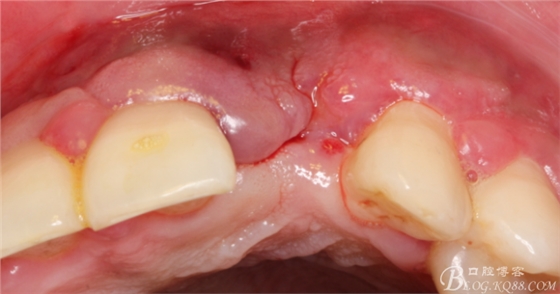

術(shù)后1個(gè)月。

術(shù)后5個(gè)月。